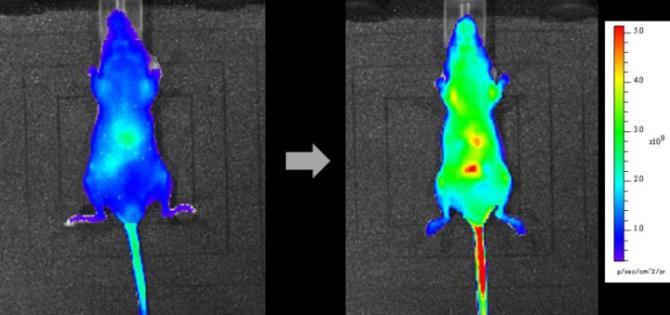

A continuación, se inyectó en los ratones una dosis de ácido ascórbico extra, elevando la concentración por encima de lo normal. En 10 minutos, la señal de fluorescencia se encendió en el abdomen, mostrando que este era el primer destino de la dosis de ácido ascórbico que fluía desde la cola. Como antes, la señal de la sonda se extendió por todo el cuerpo durante la siguiente hora, haciéndose particularmente intensa en los órganos vitales. Esta es la primera vez que los investigadores han observado directamente el ácido ascórbico administrado a un ratón.

A los ratones se les inyectó una dosis de vitamina C adicional, elevando la concentración por encima de lo normal. La señal de la sonda se extendió por todo el cuerpo durante una hora, haciéndose particularmente intensa en los órganos vitales. Esta es la primera vez que los investigadores han imaginado directamente la vitamina C administrada a un ratón. (Crédito: 2017 KAZUYUKI ISHII, INSTITUTE OF INDUSTRIAL SCIENCE, THE UNIVERSITY OF TOKYO)